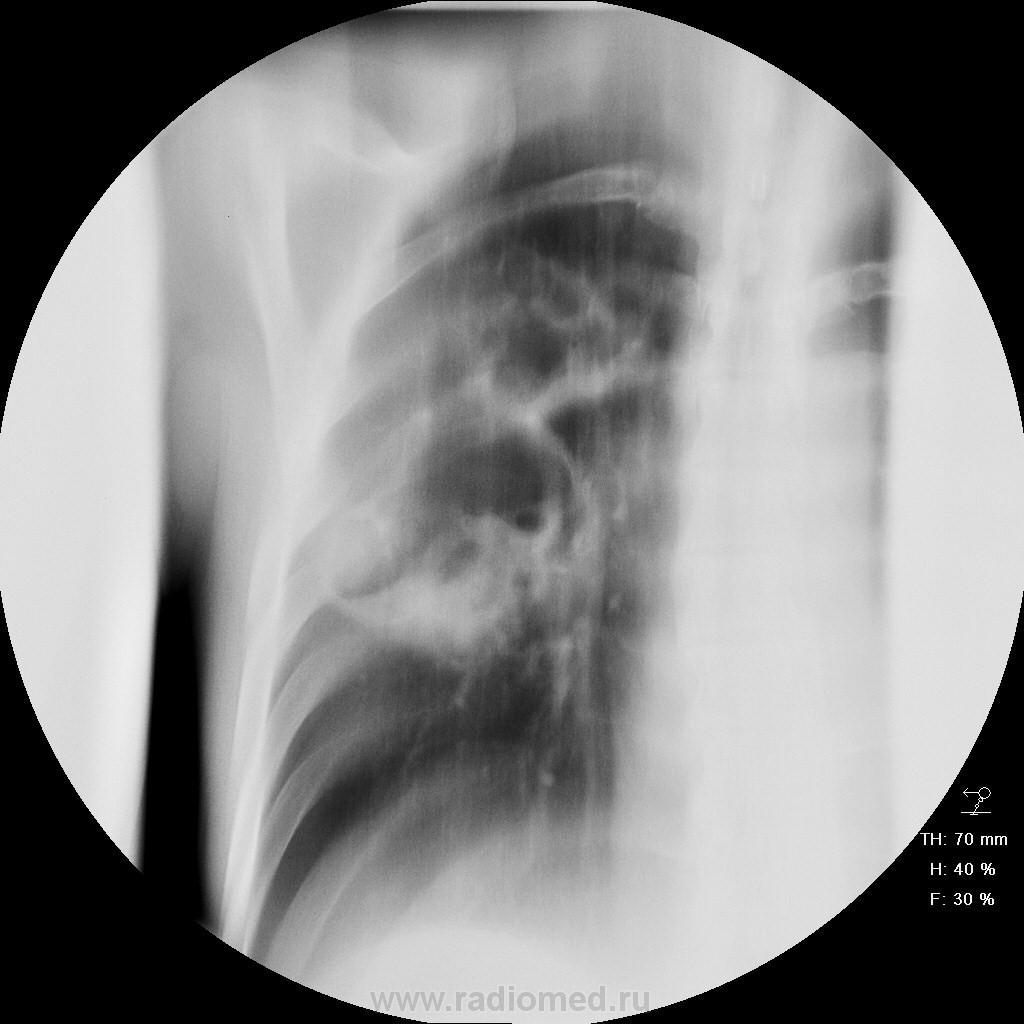

мужчина, 50 лет, социально благополучный, поступил с жалобами на температуру до 39, боль справа, утомляемость и т.д. В анализах высокое СОЭ, лейкоцитоз. Заболел остро 2 недели назад, когда в поликлинике выставили по флю пневмонию в S2 (со слов) и стали лечить... Всвязи с отсутствием положительной динамики направили к нам в пульмонологическое отделение.

полостные образования давние, с хорошо выражеными, сформироваными, плотными стенками, нет перифокального воспаления - значит не абсцедирующая пневмония. Учитывая клинику - воспалившиеся (нагноившиеся) кисты

в торак. отделении произведена резекция верхней доли , С6 нижней. 2 крупных абсцесса( нагноившиеся кисты? ). один в С2, другой в С6. в верхней доле - буллы до 3 см. в С6 , ближе к корню , -инфильтрат(пневмония).

диагноз хирурга: буллезная дисплазия. абсцессы (нагноившиеся кисты), пневмония.